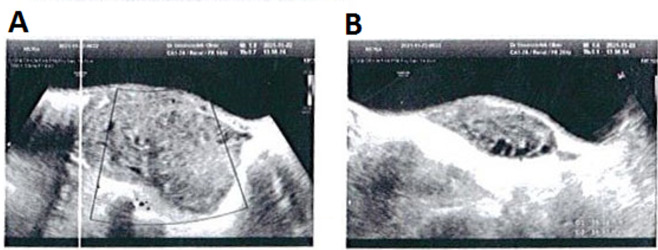

Case presentation: In this case study, we describe a case of ovarian torsion in an 8-year-old Iranian girl who came with persistent (non-colicky) right-side abdominal pain. After ultrasonographic examinations, she was identified with an enlarged heterogeneous right ovary indicative of ovarian torsion and underwent emergency laparotomy without oophorectomy.